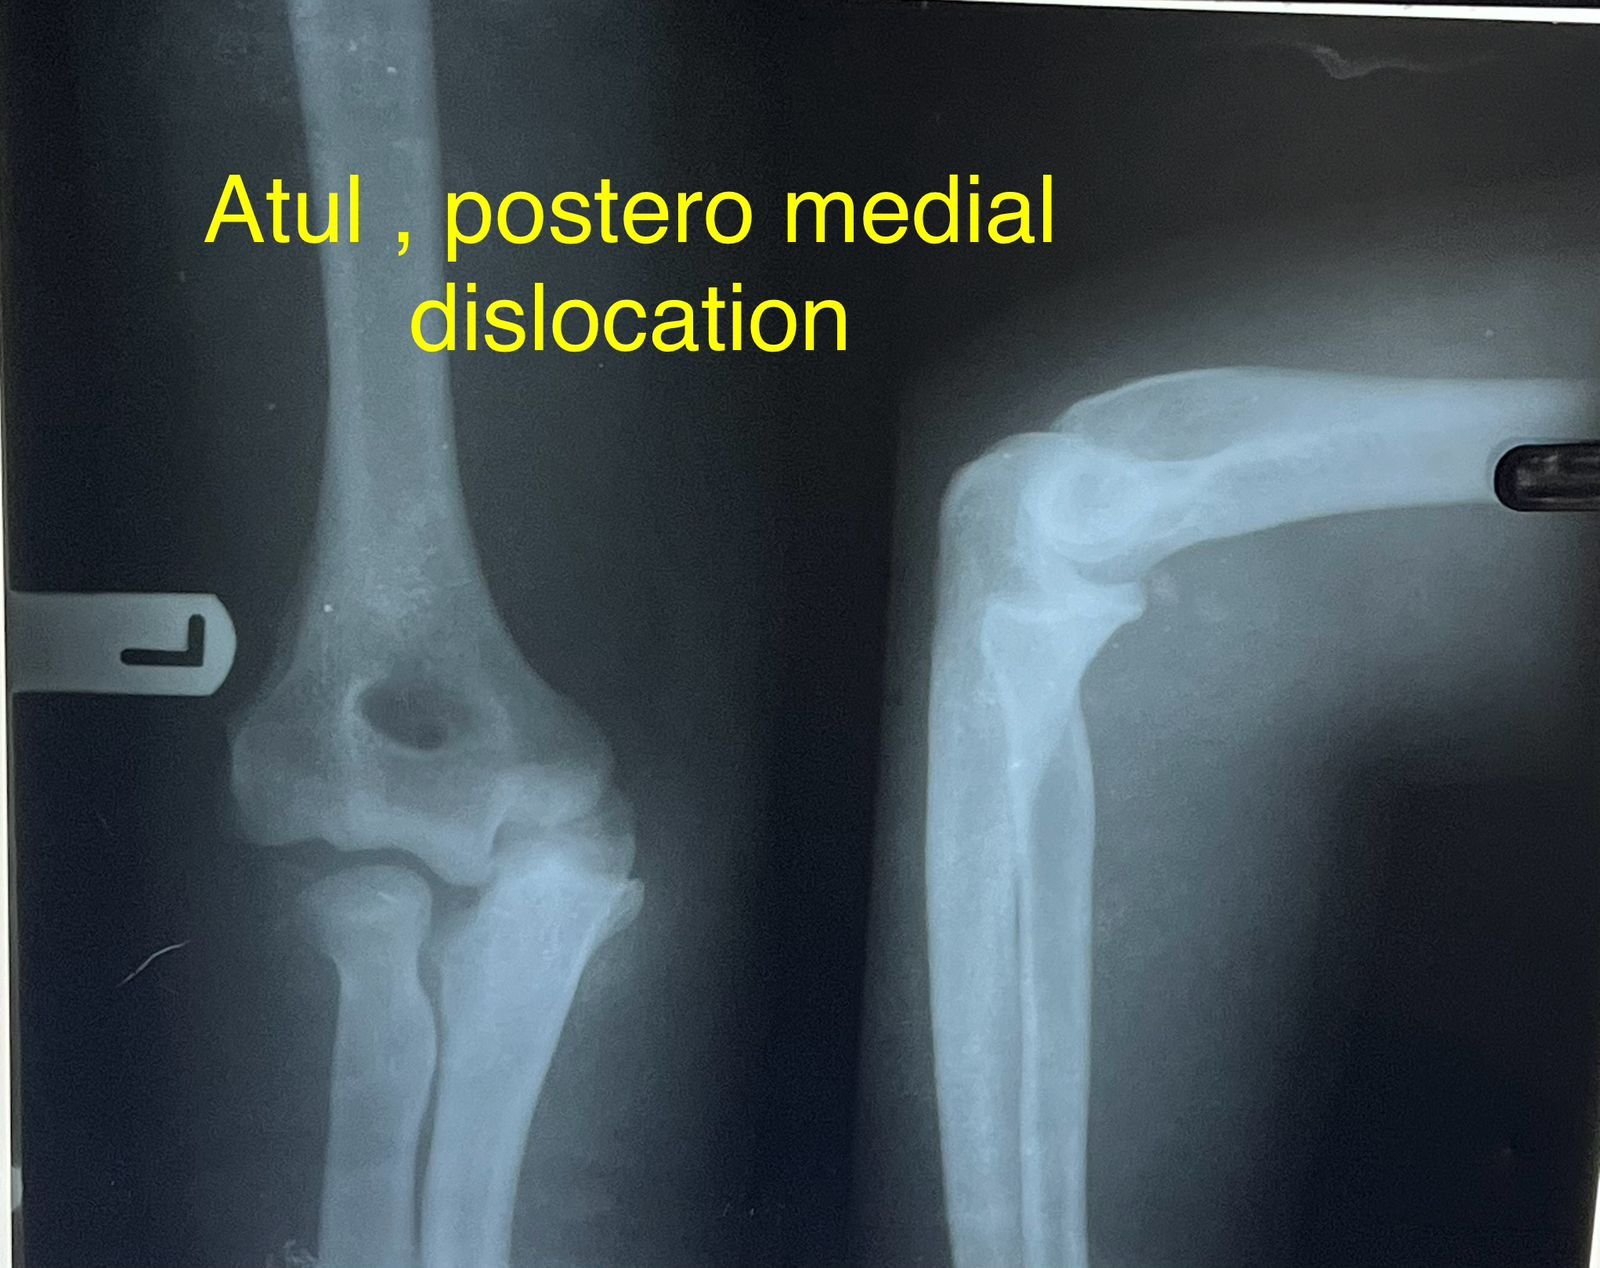

Clinic Exterior & Reception | Elbow dislocation &

operative treatment